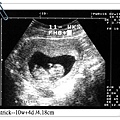

Patrick 十週過四天,身高4.18公分